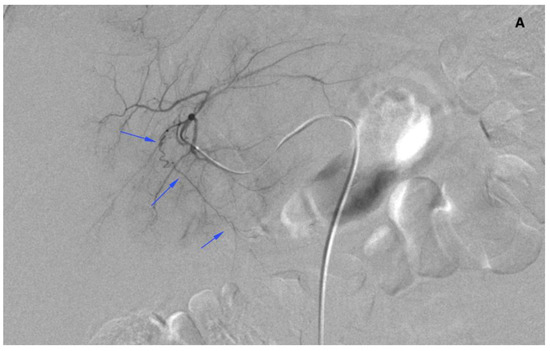

There were 20 patients after cholecystectomy. There were 30 (40%) patients with additional cystic arteries (Figure 3).

Figure 3.

Angiogram of the right hepatic artery. (A) Initially, single CA is visible (arrows) originating from the right hepatic artery division. (B) After embolization, another artery reveals multiple intrahepatic anastomoses to the gallbladder wall, and needs to be embolized. (C) There is insufficient embolization of both CA, and (D) retraction of the microcatheter reveals another CA originating proximally to the right hepatic artery division (arrows).